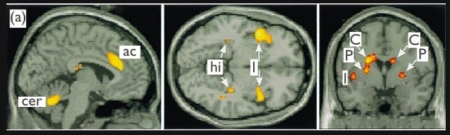

উপরের ছবিতে আমাদের ব্রেনের সক্রিয় অঞ্চলগুলো দেখা যাচ্ছে (লাল এবং হলুদ রঙ), যখন গবেষনায় অংশগ্রহনকারীদের তাদের ভালোবাসার মানুষের ছবি দেখানো হয় এবং এই প্যাটার্নটির তুলনা করা হয়েছে, যখন তারা তাদের অন্য কোন বন্ধুদের ছবি দেখে সেই সময়ে তাদের ব্রেনের সক্রিয় হবার প্যাটার্নের সাথে। অ্যাক্টিভিটিটা সীমাবদ্ধ অল্প কিছু এলাকায়: ac: anterior cingulate; , cer: cerebellum; I:insula; hi: posterior hippocampus, C: caudate nucleus, P:putamen. ( সুত্র: NeuroReport,Vol 11 No 17 27 November 2000

আমাদের ব্রেনের একটি ডায়াগ্রাম, এই আলোচনায় যে অংশগুলোর কথা বলা হয়েছে, তার কয়েকটি অংশ। সুত্র: (FEBS) Letters 581 (2007)